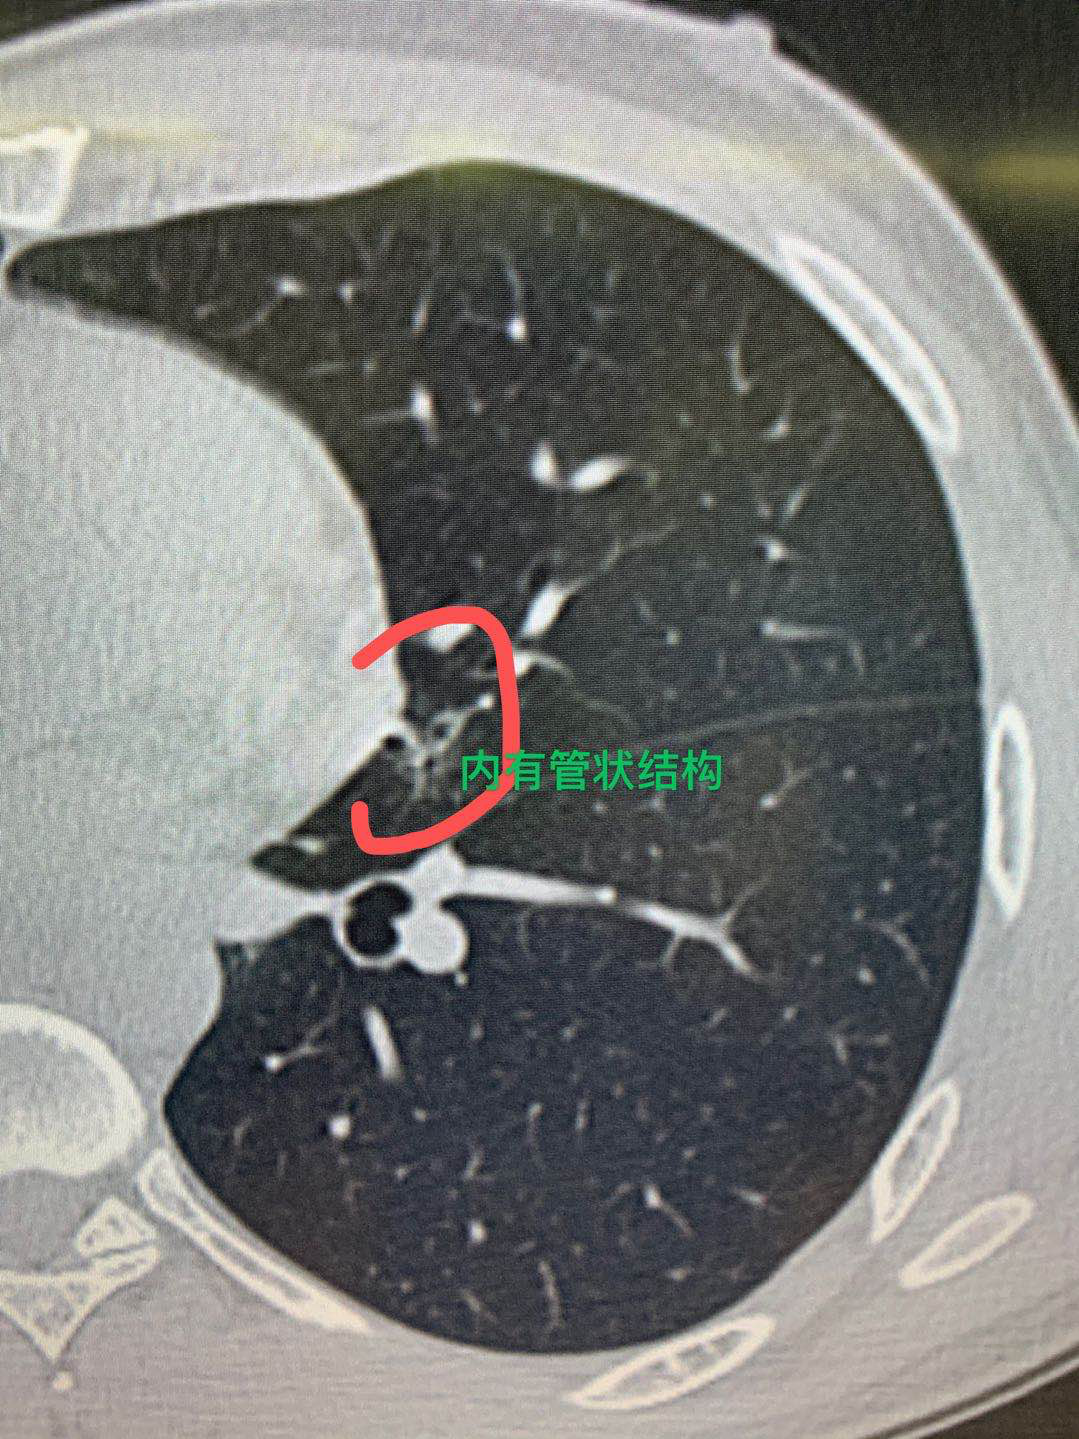

所以,他在今年复查的时候就做了1mm层厚的胸部ct检查,我们就看到这个结节非常明显,是一个磨玻璃结节,里面有空洞气管征,影像学上就高度提示,这个结节是肺癌的可能性就非常大,所以就给他做了一个胸部单孔胸腔镜下的这个舌段切除手术。

手术过程很顺利,术中的病理证实它是一个肺的腺癌,淋巴结都没问题,只是一个早期的肺癌,切除以后就完全治好了。因此,从胸部ct对于肺小结节的检查来说,应该做薄层ct扫描,再者从影像学的判断上看,这个病人病灶里面有很多小的空洞一样的表现,支气管征非常明显,这也是高度提示它是一个恶性的征象。虽然不到一公分,但是它是一个早期的肺癌表现。早发现,然后早手术以后就完全能治好。